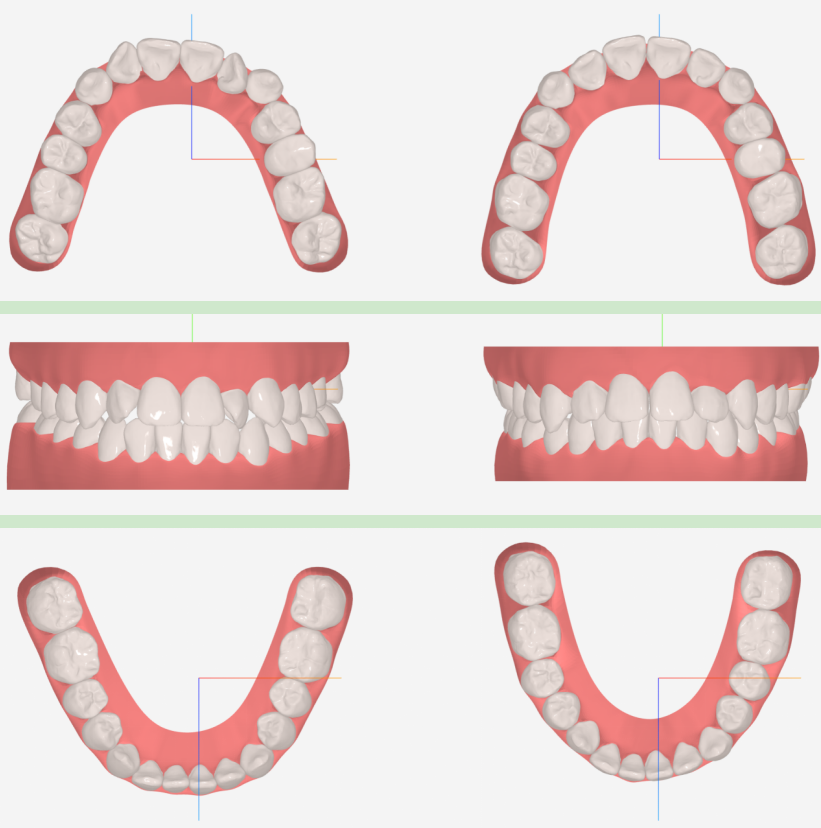

传统正畸方案设计,高度依赖医生的经验与时间投入,进行耗时的头影测量、牙齿移动模拟。AI快速目标位技术的核心,在于将海量优质病例数据与深度学习算法结合,能够基于患者初始数据,在短时间内自动生成符合生物力学原则的、个性化的牙齿移动目标位。

这意味着,医生从繁琐、重复的测量劳动中解放出来,获得了 “AI第一助理” 。它提供的不是一个冰冷的、标准化的模板,而是一个融合了数万例临床智慧的高质量起点,医生可在此基础上进行更富创造性的精细调整,尤其为复杂病例、个性化托槽设计提供了强大的决策支持。